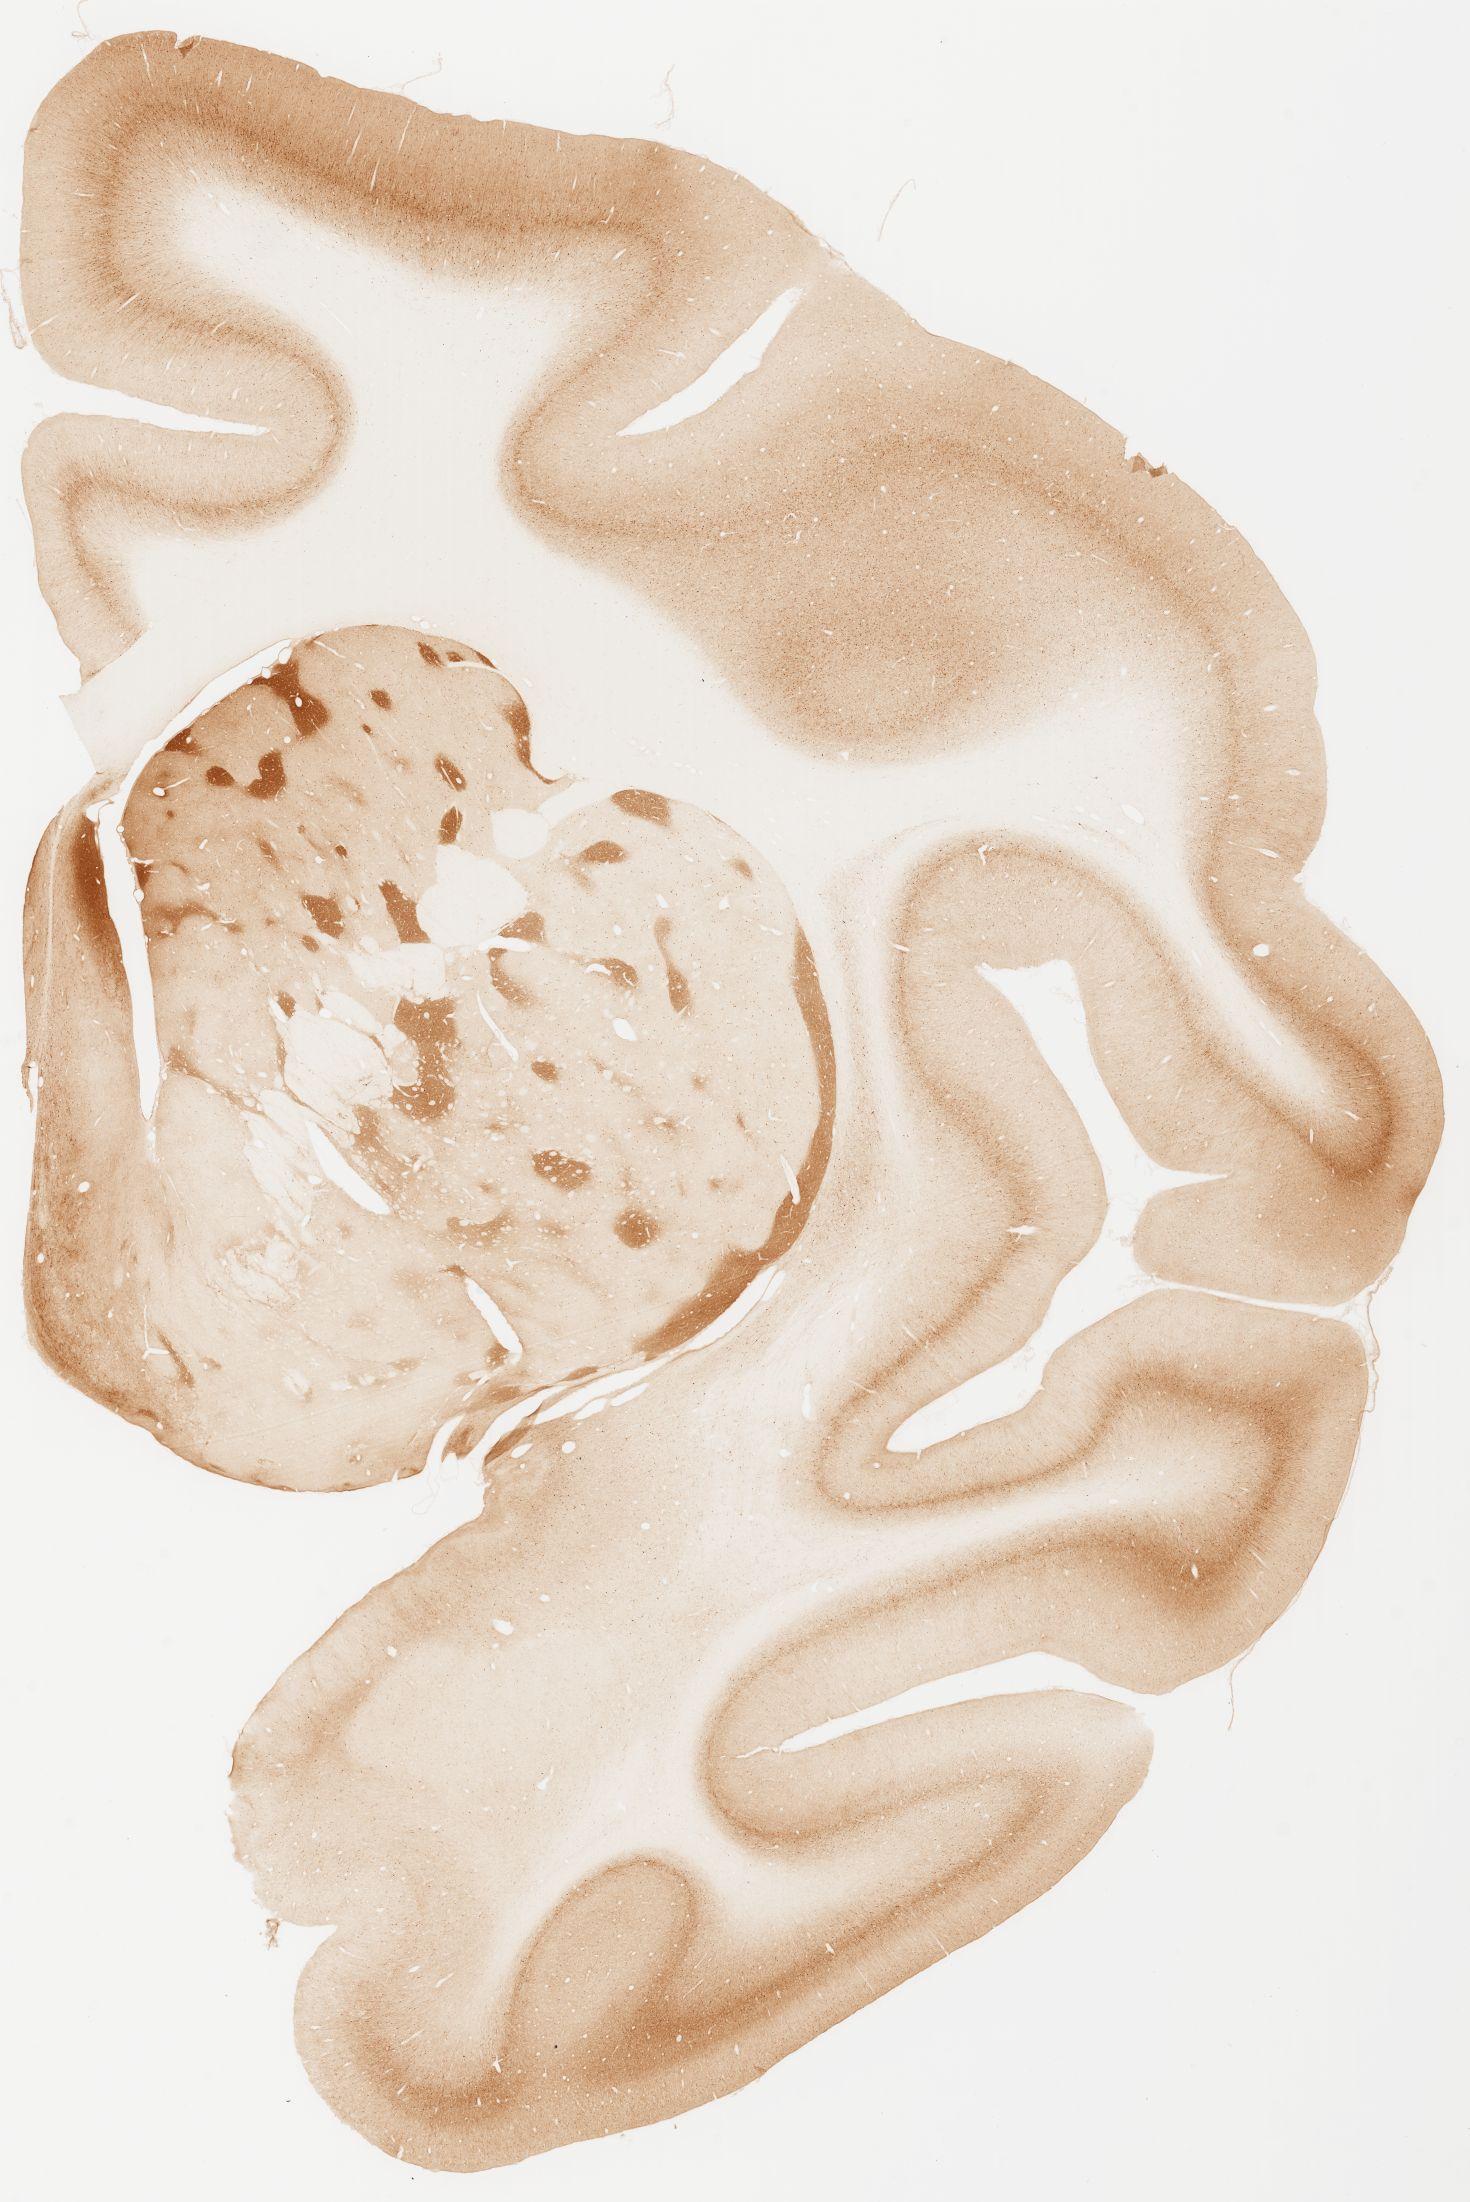

Datasets -> Macaca Fascicularis -> KChIP1, (Potassium Voltage-Gated Channel-Interacting Protein 1), coronal, immuno, Whole-Brain, adult

[ Metadata ]   ·   Source: Edward G. Jones

Displaying Sections 41 thru 80 of 92 Sections for this Dataset